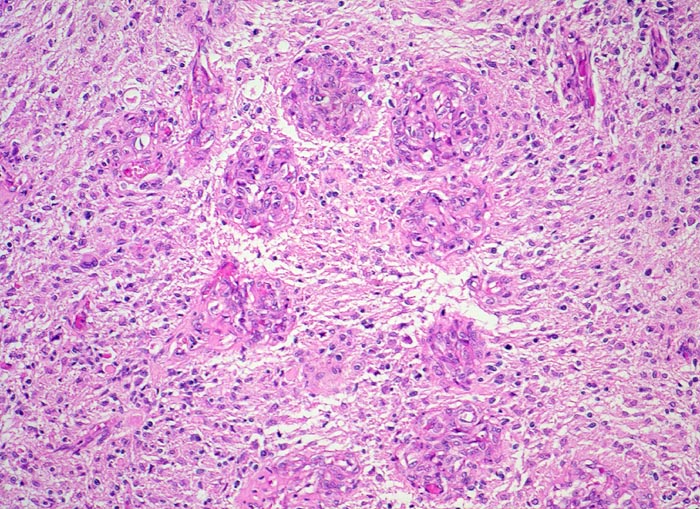

Morphologische Merkmale:

• Zellreicher Tumor mit sehr unscharfer Begrenzung zum normalen Hirnparenchym (rechts unten).

• Typische streifenförmige Nekrosen mit randständiger Palisadierung der Tumorzellen.

• Im Zentrum der Nekrose thrombosierte Gefässe umgeben von einem Saum vitaler Tumorzellen.

• Pathologische glomerulumartige zellreiche Gefässknäuel.

• Ausgeprägte Zellpolymorphie und Atypie.

• Mitosen.